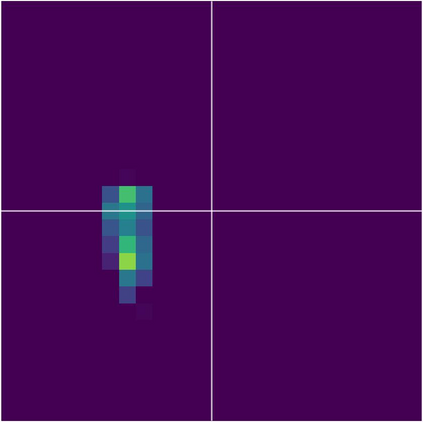

Various imaging modalities allow for time-dependent image reconstructions from measurements where its acquisition also has a time-dependent nature. Magnetic particle imaging (MPI) falls into this class of imaging modalities and it thus also provides a dynamic inverse problem. Without proper consideration of the dynamic behavior, motion artifacts in the reconstruction become an issue. More sophisticated methods need to be developed and applied to the reconstruction of the time-dependent sequences of images. In this context, we investigate the incorporation of motion priors in terms of certain flow-parameter-dependent PDEs in the reconstruction process of time-dependent 3D images in magnetic particle imaging. The present work comprises the method development for a general 3D+time setting for time-dependent linear forward operators, analytical investigation of necessary properties in the MPI forward operator, modeling aspects in dynamic MPI, and extensive numerical experiments on 3D+time imaging including simulated data as well as measurements from a rotation phantom and in-vivo data from a mouse.